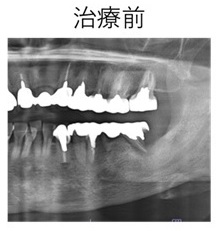

症例① 歯根破折のため左臼歯部を抜歯しインプラント治療を行なった治療例。

1

77 2